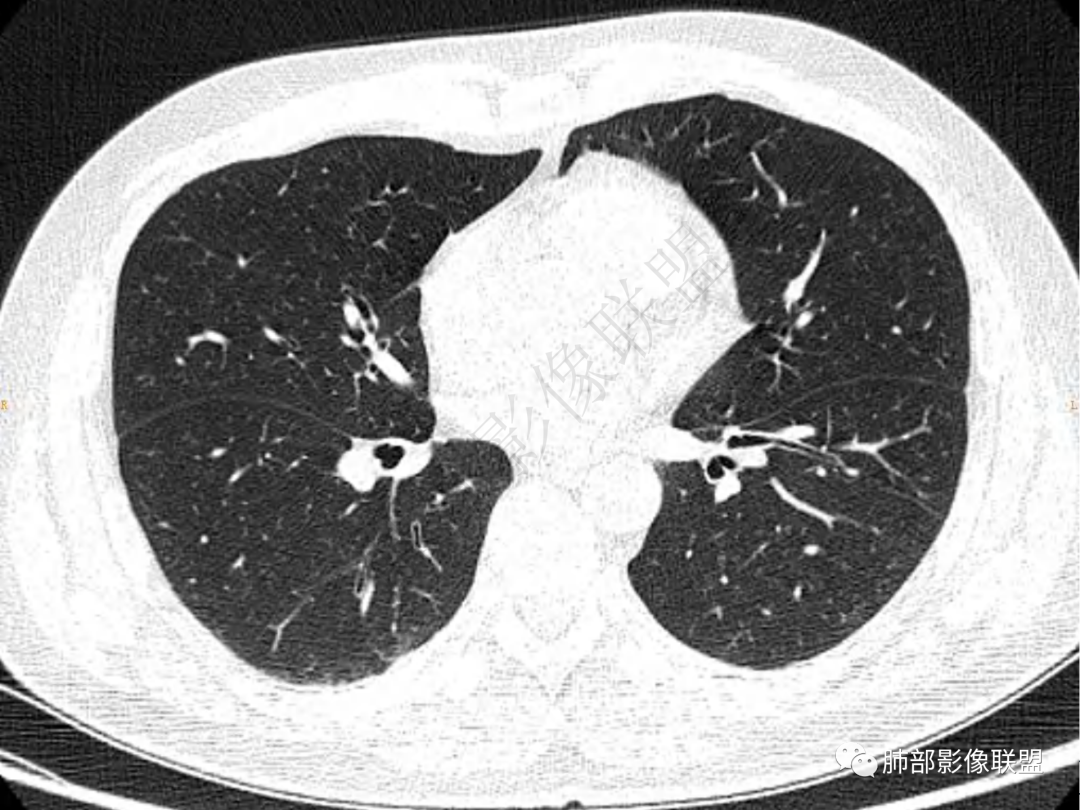

2.左肺下叶团片影,跨背段及内前基底段,实性部分类椭圆形,密度不甚均匀,可见毛刺及棘状突起,未见典型分叶及胸膜凹陷。病灶上下缘可见相应肺段支气管旁进侧出,管壁轻度增厚,未见狭窄阻塞。

3.周边较大范围磨玻璃影,边界相当模糊,小叶增厚明显。注意叶裂另一侧、左肺舌段亦可见磨玻璃影及增厚的小叶间隔。未见明确卫星病灶。

4.实性部分不均匀环形强化并显示一小范围低密度坏死区或空洞。较之肺窗,整体纵隔窗范围较小,提示病灶并不十分密实。抑或为不同时段图像。

肺脓肿:可宽基底与胸膜相连,附近胸膜增厚——炎性特点

肺脓肿:边界模糊不清,或者块影为类圆形,无明显分叶,边缘平直为主,刀切征——炎性特点三、病灶周围特点:肺脓肿:病灶非远端有片状GGO——炎性特点四、近端支气管阻塞:肺脓肿:常有引流支气管伴管壁增厚或者支气管沿洞壁走行。五:坏死壁:肺脓肿:大多壁厚,少数壁薄,没有壁结节,内壁清楚光整——炎性特点

肺脓肿:环形强化,强化较显著。如出现明显囊壁样强化甚至边缘“憩室”样突出,高度支持肺脓肿。